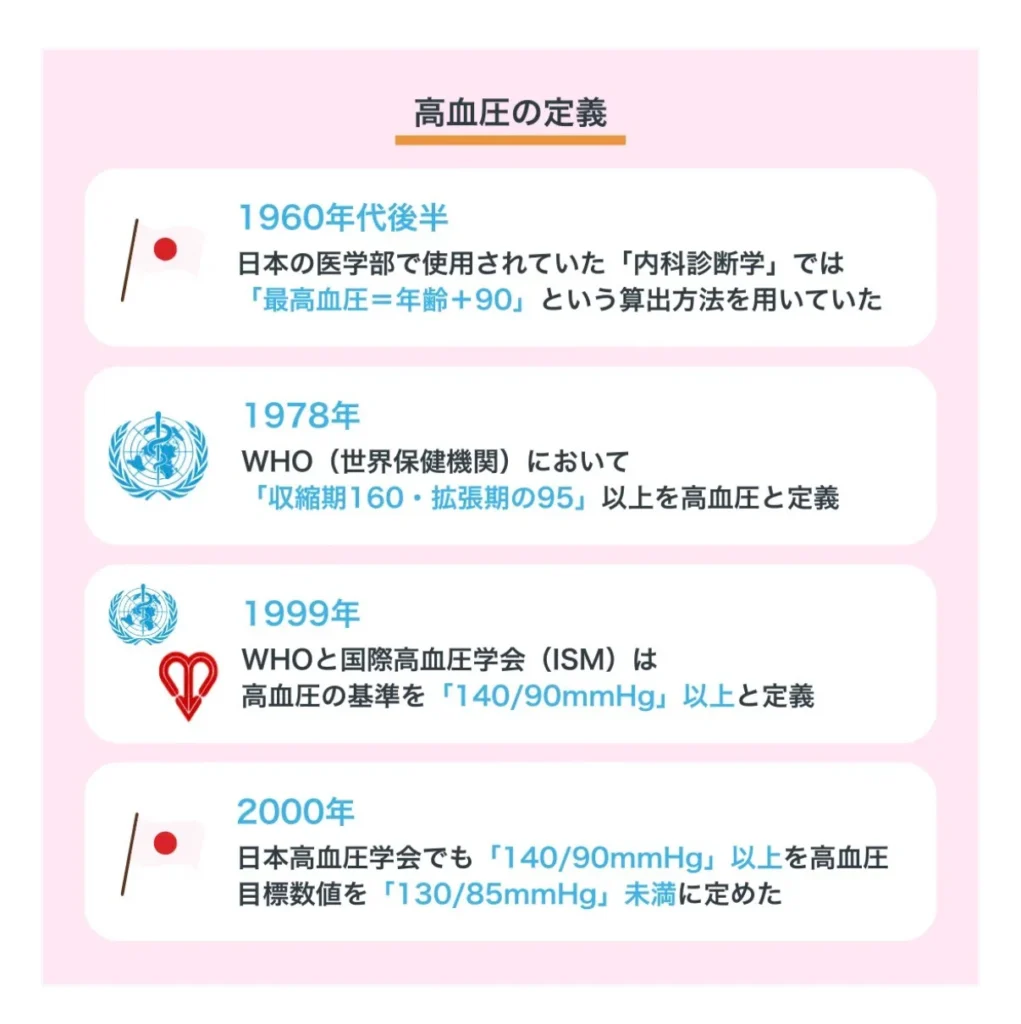

高血圧症について

○高血圧症の定義

最高血圧 140㎜Hg以上

最低血圧 90㎜Hg以上

- 基準値が下がった2000年を境に、高血圧症の該当者が大幅に増える

- 2011年の国内高血圧患者数は900万人

- 2024年 130/80以上の高血圧予備軍も含めて推定4500万人

- 治療継続をされている方は約1610万人